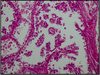

Describe picture

Disease (mc sites)

Morphology

Benign papillary projections covered with columnar secretory epithelium and underlying myoepithelial cells

Papillary Hidradenoma (labia majora/interlabial folds)

sharply circumscribed nodule

Describe picture